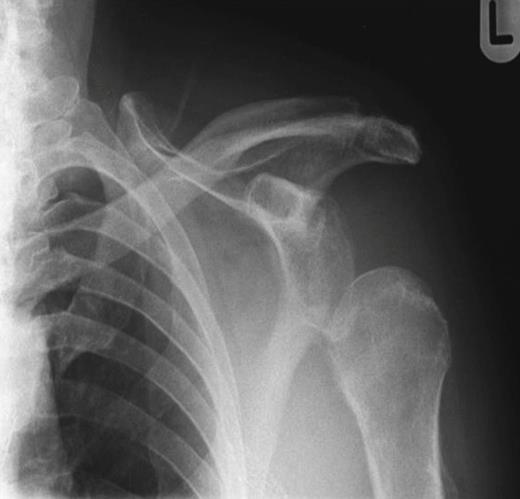

Ten weeks later a repeat orthopaedic review was requested by the rehabilitation team. There had been a slow onset and progression of oedema in the arm, with gradual progression of neurological deficit to the point at which the arm became useless and insensate. An increase in axillary bruising was noted. Also, the patient required a three-unit blood transfusion for a drop in haemoglobin six weeks after the injury. There was a thrill over the whole pectoral region and signs of venous hypertension in the arm. The left radial, ulnar and brachial pulses were normal. Repeat X ray showed subluxation of the left shoulder joint (figure 2). CT angiography revealed a distal axillary pseudoaneurysm with a sac of 15cm diameter (figure 3).

Repeat X-ray of left shoulder demonstrating subluxation of the head of the humerus